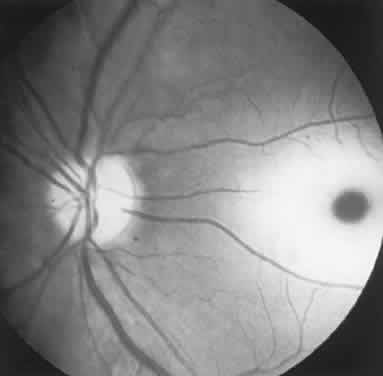

The ganglion cell layer of the retina is a principal site of abnormal accumulation of anomalous storage products, such that ophthalmoscopic changes are observable either in the form of retinal “graying” or the well-known cherry-red spot. The ganglion cell layer densely surrounds the thin fovea, which transmits the normal red color of underlying choroid (Fig. 4). The storage disorders with cherry-red spot or macular graying are listed in Table 2.27

Fig. 4. “Cherry-red spot” of advanced Tay-Sachs disease (gangliosidosis). Note the central foveal window surrounded by a ring of densely opaque retinal ganglion cell layer; also, optic atrophy.